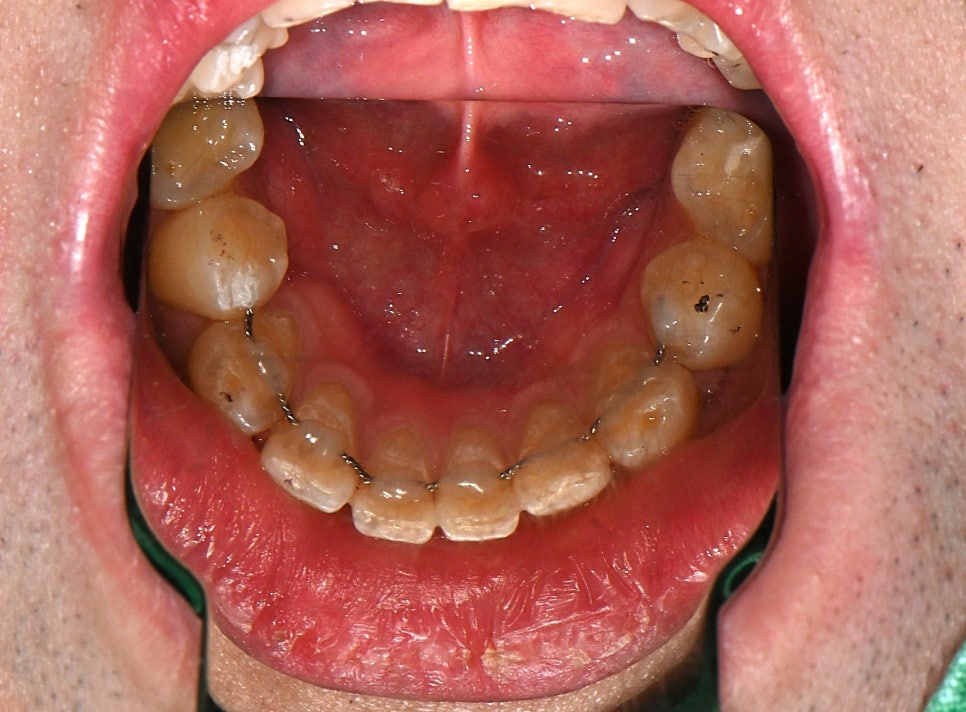

재제작한 고정 유지장치 부착 완료 후 모습입니다.

남아 있던 낡은 철사를 제거하고, 새롭게 본을 떠 정밀하게 제작한 유지장치를 다시 붙였습니다.

치아에 딱 맞게 밀착되어 앞으로 치열이 다시 흐트러지지 않도록 도와주는 역할을 합니다.